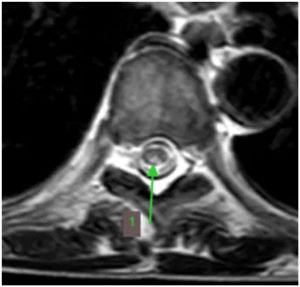

半年前,王先生开始感觉走路不稳,像踩在棉花上,还伴有肢体麻木无力。这些症状逐渐加重,最终他来到郑州大学第五附属医院神经内科二病区就诊。检查发现,他患有巨幼红细胞性贫血,维生素B12水平明显偏低。脊髓磁共振结果显示:胸段脊髓后索出现异常高信号(如图黄色箭头所示),轴位图上更是呈现出典型的倒“V”征(绿色箭头)。